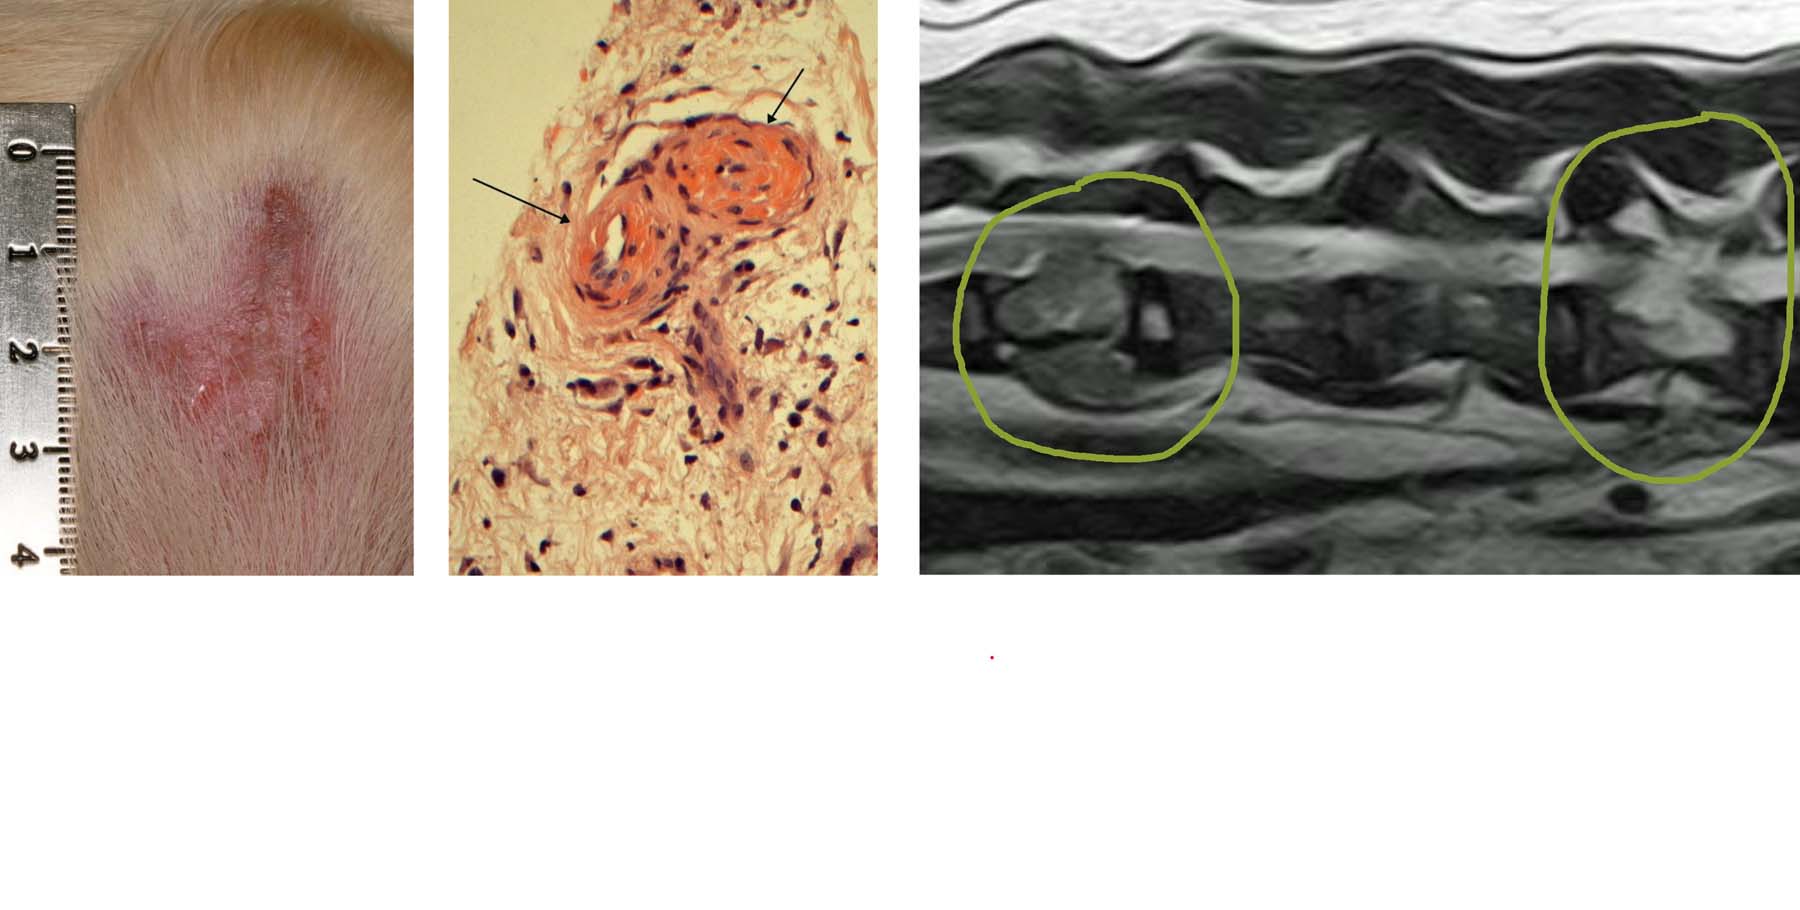

- Vasculitis or Vasculopathy – 4th slider image

- Hepatocutaneous syndrome (metabolic epidermal necrosis, necrolytic migratory erythema, superficial necrolytic dermatitis or aminoaciduric canine hypoaminoacidemic hepatopathy syndrome (ACHES)) – 5th & 6th slider images